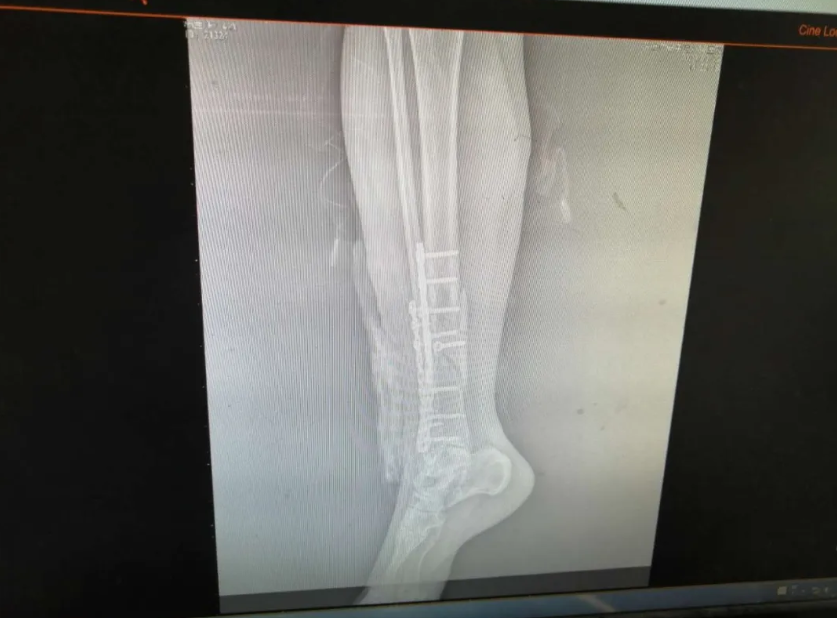

随后,医生根据杨女士的自身情况对她说明要等到患肢消肿后方可行手术,没消肿做手术的话会对术后伤口愈合不良,但考虑到其患肢自行消肿时间会比较长,所以建议予中药外敷以减轻肿胀和疼痛情况,杨女士表示接受治疗。中药外敷了几天后,效果明显,护士查房的时候问到患者感受,杨女士说第一天就感觉到效果了,明显没有之前那么痛了,于是在患肢消肿后就可以准备做手术了,谢业东主任给患者耐心讲解术前、术中、术后的注意事项以及术后的功能锻炼,杨女士在了解自己的治疗方案后,对手术更有信心了,在完善了术前相关检查后,手术于3月22日上午进行,行右胫腓骨开放复位内固定术,手术过程非常顺利,患者恢复良好,术后在医生护士的指导下进行康复功能锻炼,现已康复出院。

出院的时候,患者和家属不停地给医生道谢,表示对谢主任精湛医术的钦佩,同时一个劲的夸护士有责任感,工作中一丝不苟,态度又好。谢主任对患者的肯定表示感谢,同时叮嘱谢女士出院后患肢避免负重三个月,有不适症状的话随时复诊。